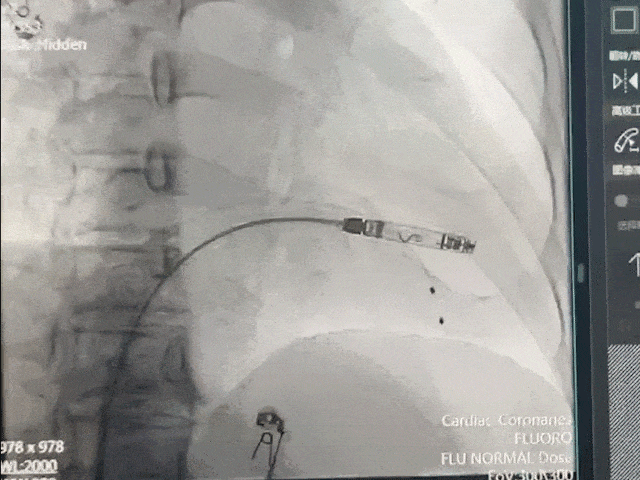

手术过程部分展示

后撤保护套筒激活无导线起搏器,调至备用起搏模式

调弯跨三尖瓣进入右室低位间隔